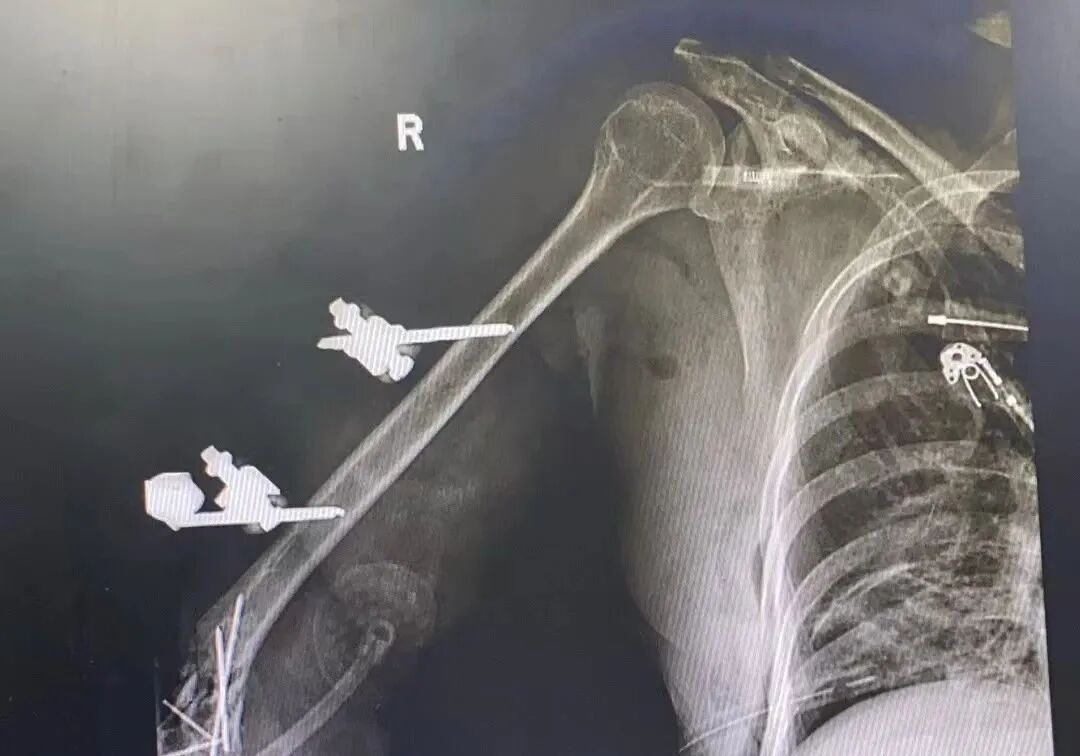

医院迅速启动急诊救治方案,急诊抢救医护人员第一时间为患者开通多条静脉通道,补液、输血,给予抗休克治疗……在进行各项救治的同时,一系列检查也在同步开展。影像学检查示:右侧肱骨下段、内外侧髁、尺桡骨近端粉碎性骨折,断端错位;右侧肩胛骨骨折伴周围软组织及肌间隙积气。辅助检查:右肩关节+右肘关节+右腕关节CT示:右侧肩胛骨骨折伴周围软组织及肌间隙积气;右侧肱骨下段、内外侧髁、尺桡骨近端粉碎性骨折,断端错位,邻近软组织肿胀并积气;颅脑+颈椎+胸部+腹部+腰椎CT示:颅脑CT平扫见顶枕部左侧皮下血肿;右侧第2/3/4/5前肋骨折,断端错位,右侧第7/8前肋局部欠光整,不全性骨折不除外,右侧肩胛骨局部骨折,右侧肩背部皮下多发积气;双肺炎症伴双侧胸腔积液;腰2椎体左侧横窦局部凹陷。

经过紧张、快速有序的抢救,完善床旁相关检查,马女士生命体征才逐渐恢复平稳,当晚急诊全身麻醉下行“右上肢清创血管神经肌腱探查修复+骨折复位内固定+外固定架固定+VSD负压吸引术"。这一复杂且关键的手术,对于稳定马女士右上肢伤势以及后续恢复,起到了至关重要的作用。